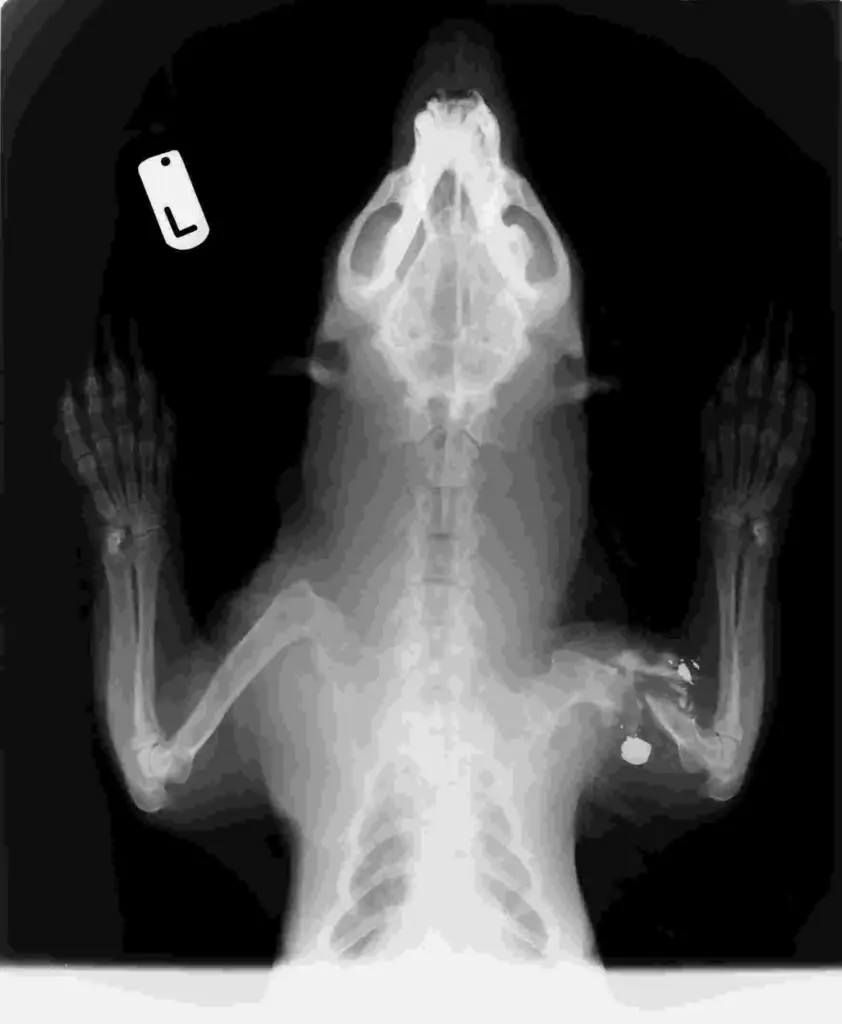

Rescued after being found in a pool of blood on the roadside, this poor male badger was rushed to the centre for treatment. Whilst we all, initially, thought it to have been hit by a car, an X-ray and examination soon exposed a far more disturbing truth.

The badger had been shot in the leg, leaving its bones in pieces. Not only that, but there were stamp marks on his head, causing massive damage to the teeth, gums and tongue. After all of this suffering, he had then been dumped on a road, in the path of on-coming traffic.